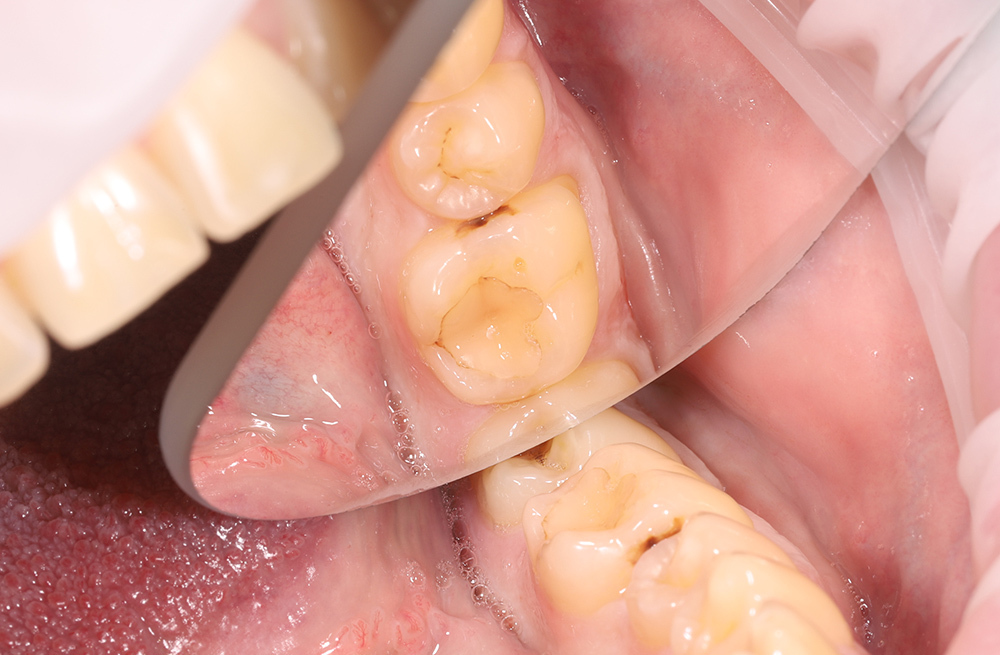

Восстановление жевательного зуба при кариозном поражении на боковой стенке